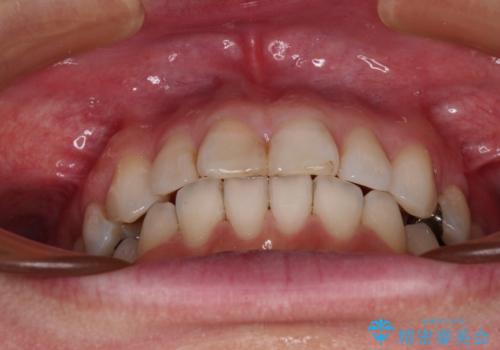

【モニター】前歯のデコボコを治したい インビザラインを用いた矯正治療

- 前歯のデコボコを治したいとのことで来院された患者様です。

上下顎ともに歯列全体の後方移動とIPR(歯と歯の間を削る)によってデコボコが解消するように設計し、インビザラインにより治療を行うこととしました。

しっかりと装着時間を守ってくださったのですが、途中妊娠にともなう悪阻や出産といったイベントがあり、予定よりも治療期間が長くなりました。